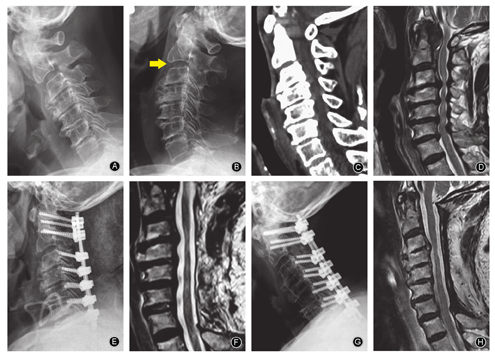

对存在节段不稳定者可行后路侧块或椎弓根螺钉内固定术,稳定颈椎同时矫正后凸畸形。传统观点认为对后凸畸形的患者行单开门椎管扩大成形术后脊髓不能有效漂移,对临床症状改善不利。但最新文献表明,术前颈椎曲度与椎管扩大成形术后脊髓后移程度、神经功能改善率无明显相关性[22];椎管扩大椎板成形术后,由于脊髓自身形态的恢复也可获得良好的神经功能改善。对上、下颈椎同时存在广泛压迫的特殊类型的脊髓型颈椎病,以后路椎板切除内固定手术为宜,因前路减压及重建操作很困难,且存在较大风险(图4)[23]。